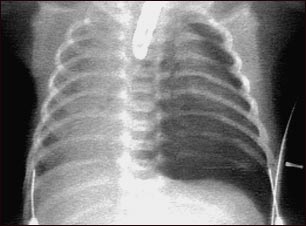

Neumotórax, radiografía de tórax

El neumotórax ocurre cuando se filtra aire desde el interior del pulmón hacia el espacio entre el pulmón y la pared torácica, ocasionando un colapso del pulmón. La oscuridad al lado derecho de la imagen indica la presencia de aire fuera del tejido pulmonar.